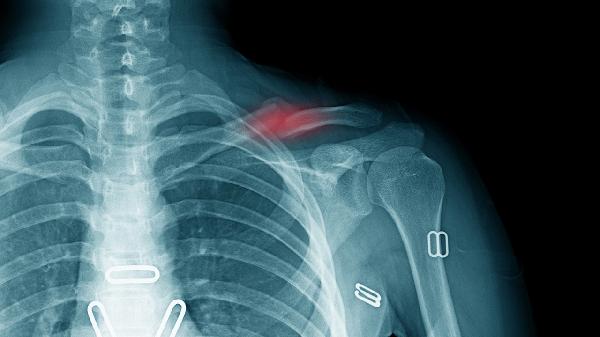

锁骨骨折恢复期需保持均衡饮食结构,建议分5-6次少量进食减轻胃肠负担。适当增加猕猴桃、草莓等维生素C丰富的水果促进胶原合成,同时配合医生指导的康复训练。避免吸烟饮酒等影响骨愈合的不良习惯,定期复查X线观察骨痂生长情况。睡眠时保持30°半卧位可减少骨折端移位风险,日常活动需佩戴锁骨固定带保护。